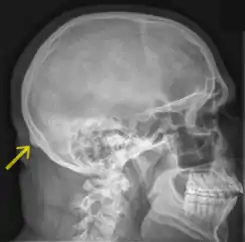

![]() Radiografía de un cráneo humano en vista lateral. Inion indicada por la flecha amarilla. | ||

El inion es la proyección más prominente del hueso occipital en la parte posterioinferior del cráneo humano. El ligamento nucal y el músculo trapecio se insertan a este nivel.

El término protuberancia occipital externa (protuberantia occipitalis externa) se utiliza a veces como sinónimo, pero con mayor precisión el término "inion" se refiere al punto más alto de la protuberancia occipital externa.

El inion se utiliza como un punto de referencia en el sistema de 10 a 20 en la grabación de electroencefalograma (EEG).